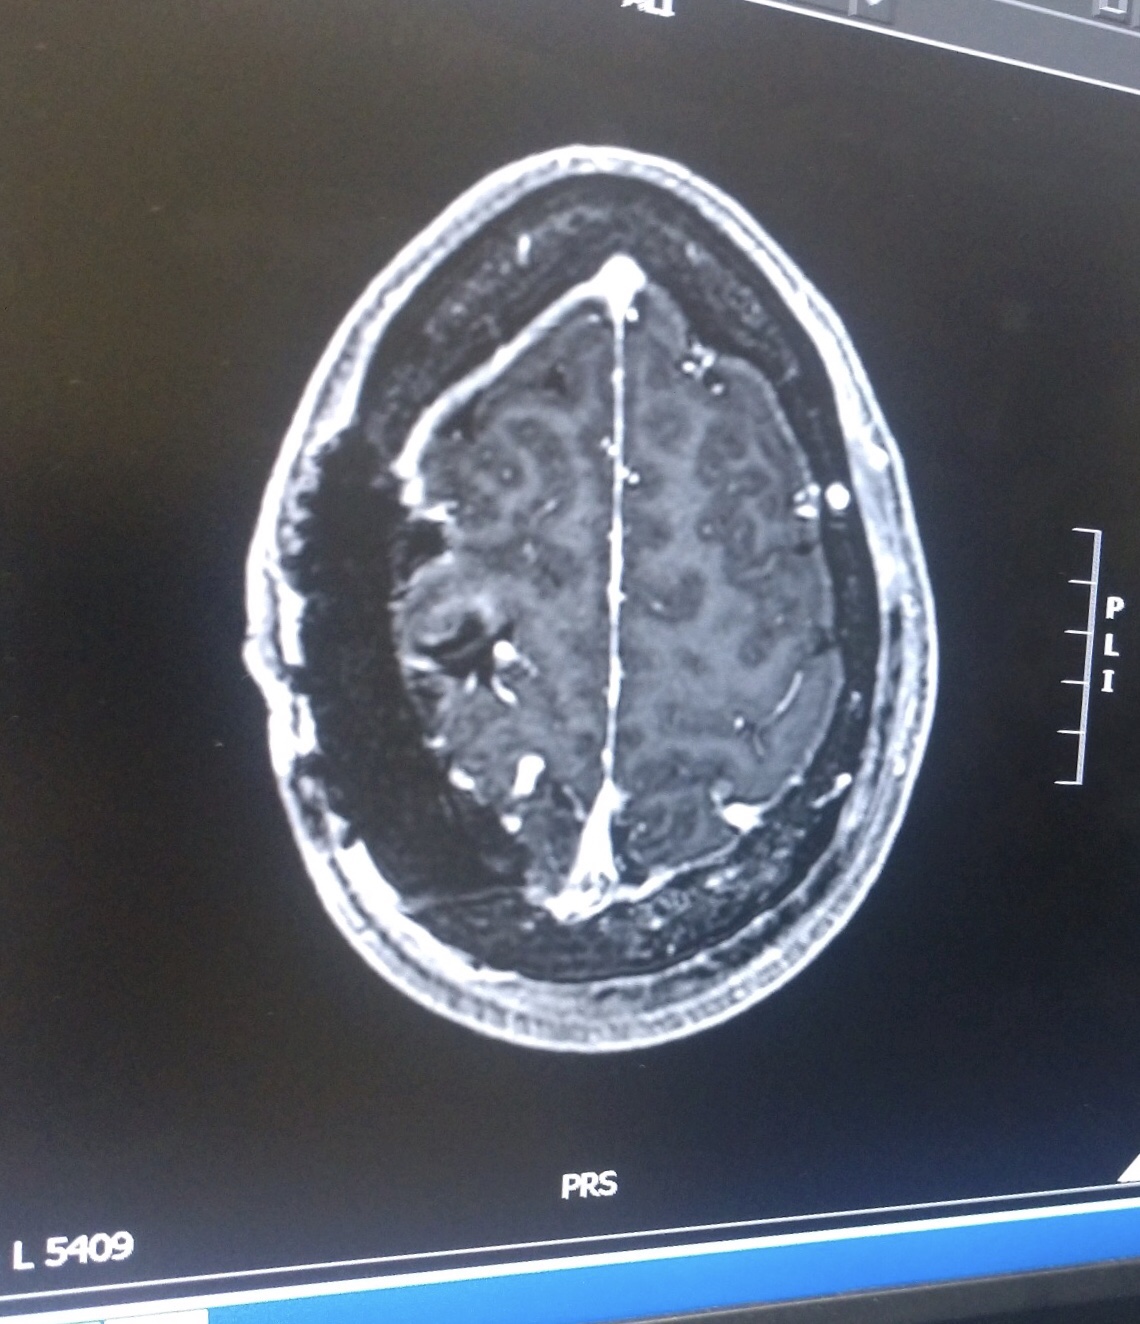

Over the next several hours, I was subjected to test after test, and answers began to come. First, seizure activity was confirmed. Then, we were told about the brain tumors; “several.” Finally, for the first time, we heard the word Neurofibromatosis II.

Although this news was detrimental, all I could do was laugh. I laughed so hard I cried. Were they sure they had the right scans? I couldn’t even pronounce the word; ‘Neurofibromatosis.’ I told the neuro that he had to be wrong; afterall, the EMT had assured me this was only a pinched nerve.